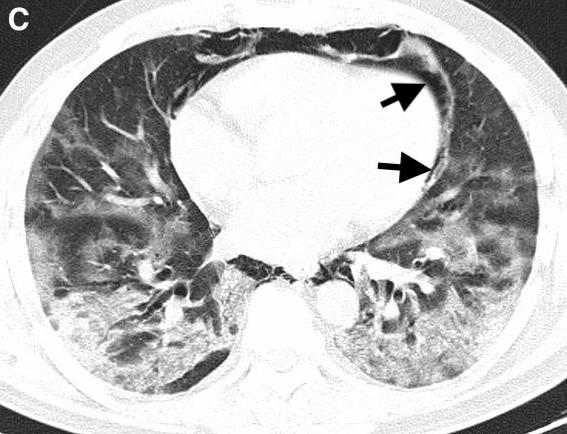

On hospital day five, the patient developed dysphonia, dysphagia, pleuritic pain, and subcutaneous emphysema in the supraclavicular region. His oxygen saturation was maintained at 97% with O2 at 3L / min through nasal cannula. A chest X-ray (Figure 1) and CT scan showed cervico-mediastinal emphysema (Figure 2) with pneumopericardium (Figure 3) and worsening lung infiltrates without pneumothorax.

Figure 3.